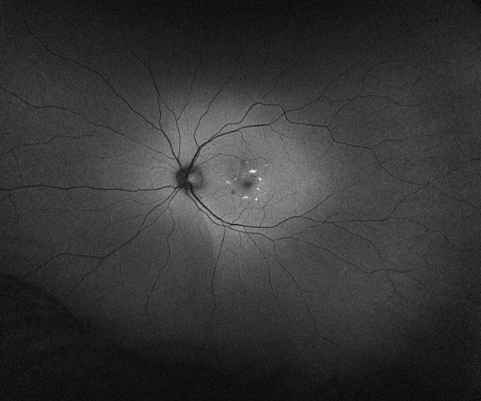

Not to keep you in suspense, but the news is as good as it could be. He said, with brisk certainty, it’s Pattern Dystrophy. A genetic (not bizarre tropical) condition where the garbage removal system of the eyes doesn’t do all it’s supposed to and leaves mounds and caverns in the macula. The prognosis, he said, was good. Very very few people with this condition lose their sight and most are able to drive or read a newspaper their whole lives (or until they get something else). It definitely isn’t macular degeneration. He was, he said, comfortable leaving it there and just monitoring it. We could also do a formal diagnosis, and it turns out that The Dude Who Studies Genetic Retinal Diseases works at Mass Eye and Ear. So I’ll go do the formal thing and maybe enroll in a study. This is different than not having ANYTHING wrong with my eyes. I am now able to identify some … wobbles in my vision. Some of what I was figuring was just being that age is actually these deposits.

The only thing I need to do is to look at the Amsler Chart regularly to make sure no enterprising blood vessel decides to make a break for it through the thinner covering of my eye. This is the test I unexpectedly failed in the first appointment. Look at the dot in the middle of the grid one eye at a time. Do all of the lines stay straight? They don’t for me. There are wiggles in it. I was charmed when I first saw it. How do they do that optical illusion? But the illusion was actually the distortions in my macula.